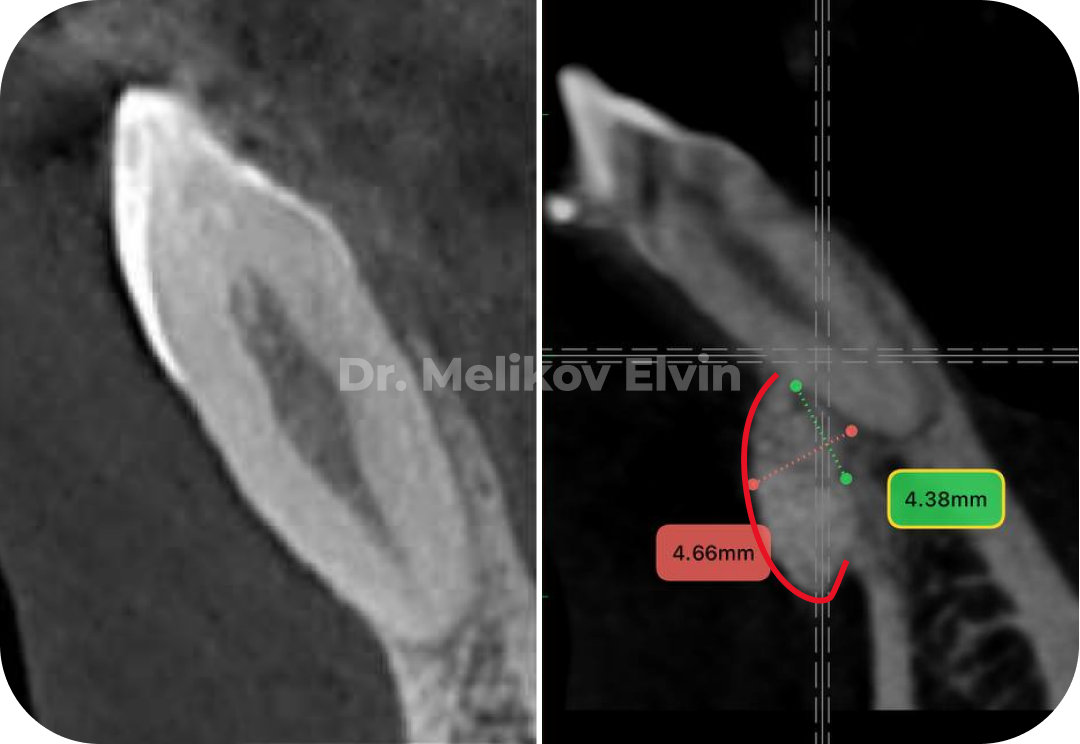

🔹Контроль КТ через 4 месяца после операции.

До костной пластики.

После костной пластики.